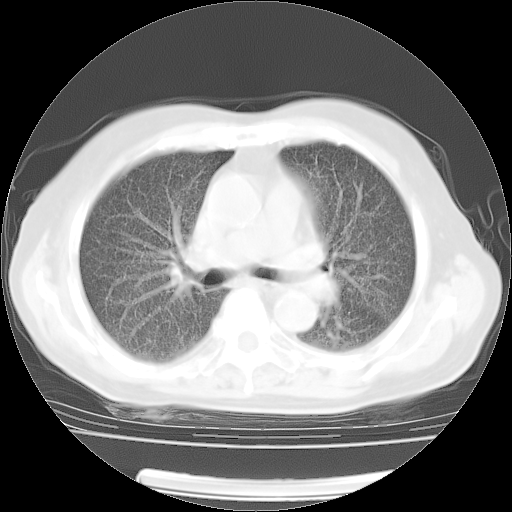

4月14日肺部CT

楼主| 发表于 2010-4-28 16:51 | 显示全部楼层

楼主| 发表于 2010-4-28 16:53 | 显示全部楼层

肺部CT平扫未见异常。